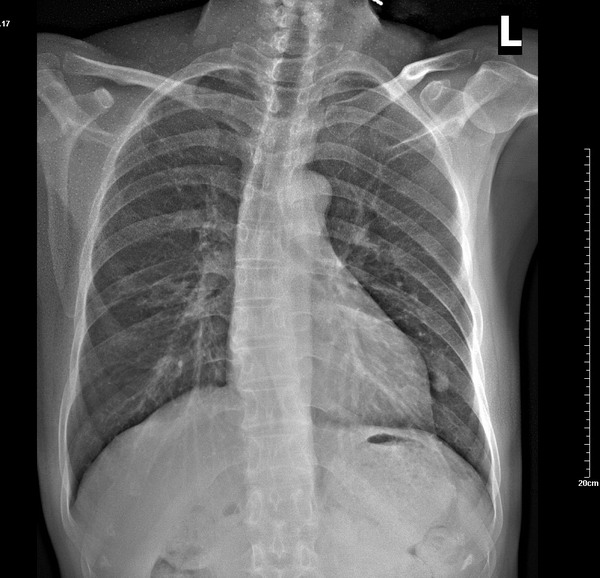

x7532。右肺病变,结果是:右下叶背段肺结核。

原贴地址:那是2009年1月19日的片子: